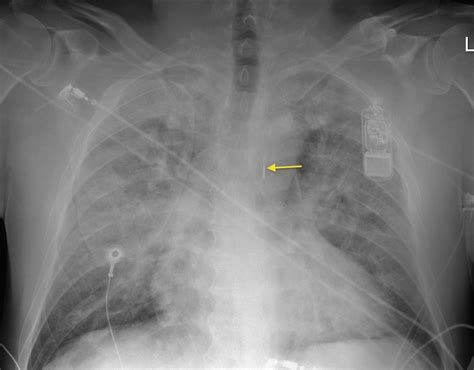

Intra-aortic Balloon Pump - Radiology At St. Vincent's University Hospital

Intra-aortic balloon pump - Radiology at St. Vincent's University Hospital www.svuhradiology.ie

balloon pump aortic intra tube coiled ng radiology carina oesophagus malpositioned svuhradiology ie